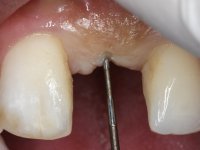

The orthodontic active treatment with straight wire technique (with high anchorage) lasts 14 months, followed by 6 months of contention with an acrylic removable prosthesis with a vestibular arch. The orthodontic treatment included a relatively rigid stabilizing wire and an open coil spring placed between the right central incisor and the left lateral incisor in order to obtain adequate space for the placement of an implant and crown in the left central incisor spot.